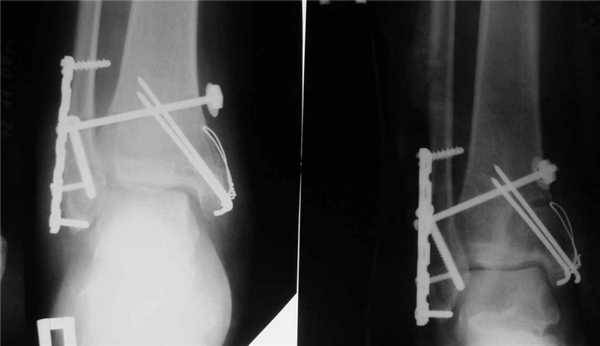

Открытая репозиция с внутренней фиксацией

Метод применяют для лечения сложных переломов, когда невозможна ручная репозиция отломков и удержание их в нужной позиции с помощью гипса. Чтобы сопоставить костные фрагменты и надежно зафиксировать их, используют погружные элементы и конструкции:

- болты-стяжки;

- винты;

- болты с клеммами-накладками;

- спицы Киршнера;

- болты с гибкой тягой;

- лавсановые ленты и прочее.

Открытая репозиция обеспечивает одномоментное точное сопоставление отломков и их надежную фиксацию. После операции нередко сохраняется ранняя опороспособность конечности, что позволяет нагружать ее вскоре после операции. И тем не менее многие специалисты уверены, что ни один из методов открытой репозиции не может обеспечить полной неподвижности костных фрагментов. Поэтому после операции пациентам требуется дополнительная гипсовая иммобилизация.

Если сопоставить отломки невозможно, проводится оперативное лечение. Внутреннюю лодыжку укрепляют при помощи винта, а наружную - при помощи пластины. При наличии разрыва связок между большеберцовой и малоберцовой костями их соединяют спонгиозным винтом. После оперативного вмешательства на травмированную конечность на 6 недель накладывается гипсовый сапожок. В дальнейшем реабилитологи назначают пациенту ЛФК после перелома лодыжки (видео есть в интернете).